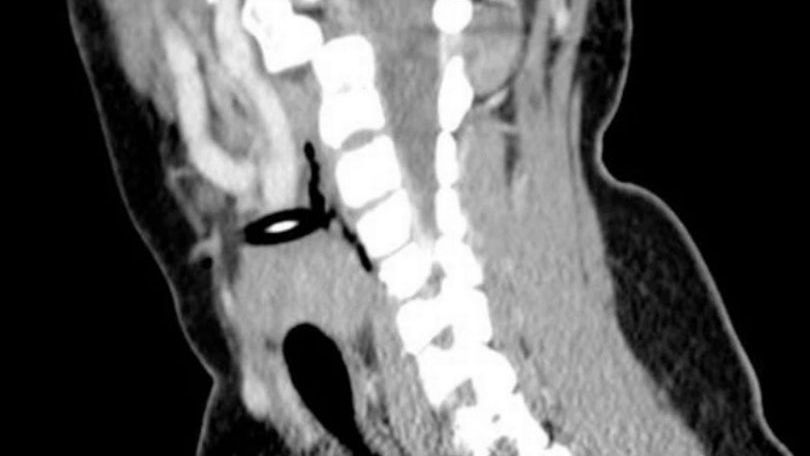

La mecánica del accidente fue tan terrible e impactante que la niña cayó sobre la punta del lápiz, el que se le incrustó en el lado izquierdo del cuello. Tras el incidente, la víctima fue trasladada de urgencia al hospital regional y allí informaron que sufría un ‘Traumatismo pediátrico penetrante en el cuello’.

Además se estableció que ‘el lápiz estaba alojado en su arteria carótida común izquierda causando un bloqueo total’. Pero como los signos vitales eran estables, los profesionales procedieron a realizarle una intervención quirúrgica para retirarle el objeto.